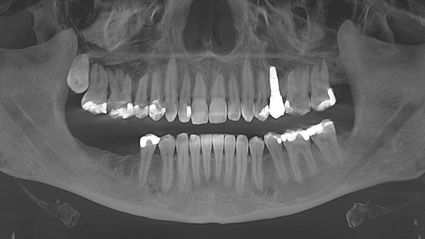

Meine Symptome, darunter Gelenkschmerzen, neurologische Probleme und Sehstörungen, nahmen trotz der Behandlung langsam aber stetig zu. Meine Symptome - vor allem die neurologischen - verschlimmerten sich, nachdem ich nach einem Zahnverlust und einer umfangreichen Wurzelbehandlung ein Titanimplantat erhalten hatte.

Ich besuchte die SWISS BIOHEALTH CLINIC im März 2019, nachdem ich alles über ihren ganzheitlichen biologischen Ansatz in der Zahnmedizin für Metallimplantate gelesen hatte, und wusste, dass dies ein neuer Schritt auf meinem Weg zur Gesundheit war. Unmittelbar nach der Entfernung des Titanimplantats begann sich mein Körper zu entspannen, die anhaltenden Schmerzen in meinem linken Ellbogen verschwanden und meine Sehkraft auf dem linken Auge kehrte zurück.